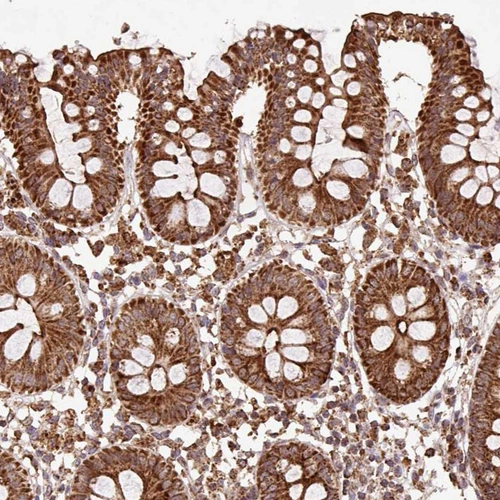

Immunohistochemical staining of human fallopian tube, gastrointestinal, heart muscle and kidney using Anti-ATP5A1 antibody HPA040622 (A) shows similar protein distribution across tissues to independent antibody HPA044202 (B).